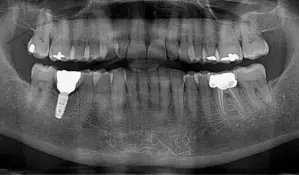

3. Panorama røntgen (OP)

• Formål

Panorama røntgen giver et overblik over hele munden, herunder tænder, kæbe, kæbeled og bihuler.

• Hvordan det tages

Du står oprejst, mens en maskine drejer rundt om dig i ca. 20 sekunder. Herved tages et billede af din mund, kæber og bihuler, der vises samlet på ét røntgenbillede.

• Hvornår det er indiceret

Panorama røntgen bruges til at få et overordnet billede af tænder og kæber, hvilket er nyttigt til at planlægge større behandlinger som tandimplantater, protesebehandling eller kirurgiske indgreb.

Panorama anvendes også ved behov for vurdering af kæbeled og bihuler, samt inden fjernelse af visdomstænder for at vide præcist, hvordan de ligger.

Panoramarøntgen (OPG) fra tandlægerne Ølandshus på Amager med synlige fyldninger og implantat.